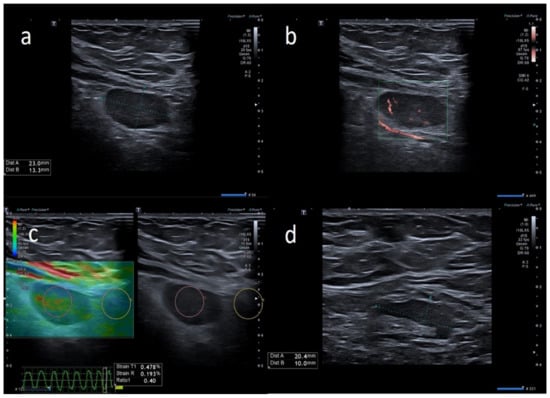

| W | 37 | Pfizer | Axillary ipsilateral to vaccine injection | Three days after first dose vaccine, axillary swelling present | Melanoma 5 years ago | 5 | Variable: from 1.5 to 2.0 cm. | Ovular | Assimetric cortical thickening with hilum evidence | Prevalent hard pattern | Central and peripheral vascular signals | Normalized to 45 days |